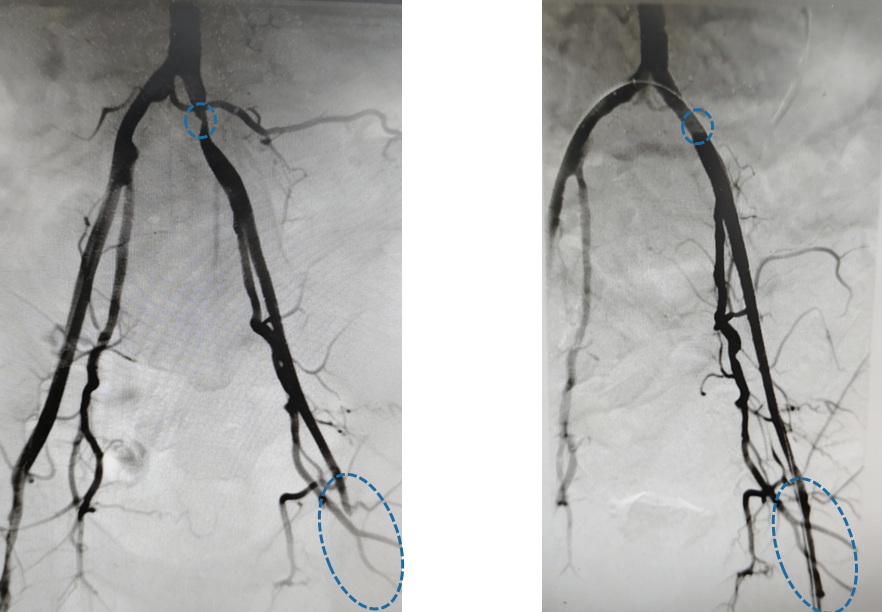

彻底清除“路障”后,医生利用生物补片对血管进行了加宽修补,就像给衣服打补丁一样,既扩大了血管管径,又保证了血管壁的完整性。随后,在髂动脉关键部位精准植入支架,重新打通了从腹主动脉到下肢的血流主干道。

术前(左)血管因闭塞而“中断”,术后(右)血管通畅,血流直达足底

手术效果立竿见影。术后第一天,杨先生那条冰冷的左腿就变得温热,疼痛感消失。经过精心的术后护理,伤口愈合良好,顺利拆线出院。此次门诊复查,杨先生特意走了几圈给医生看,步伐稳健,再也没有出现那恼人的疼痛。“太感谢刘主任团队了,这次手术做得彻底,这腿算是真保住了!”